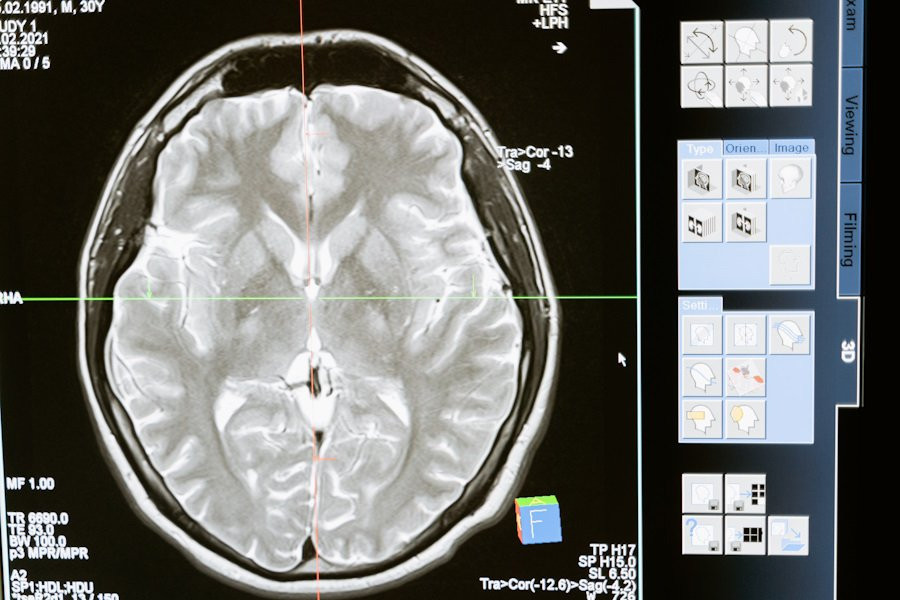

Генная терапия имеет потенциал для лечения множества тяжелых генетических заболеваний головного мозга, для которых на данный момент нет эффективных лекарств. Одобренные FDA формы аденоассоциированных вирусов (AAV), широко используемые для доставки генов, сталкиваются с трудностью проникновения через гематоэнцефалический барьер, что снижает их эффективность.

Гематоэнцефалический барьер — это высокоселективная мембрана, которая отделяет кровь от мозга и защищает его от вредных веществ. Преодоление этого барьера долгое время было серьёзной проблемой для учёных, разрабатывающих безопасные и эффективные методы генной терапии.

Команда исследователей разработала первый в своём роде аденоассоциированный вирус (AAV), нацеленный на человеческий белок. Этот вирус связывается с рецептором трансферрина, который высоко экспрессируется в гематоэнцефалическом барьере человека.